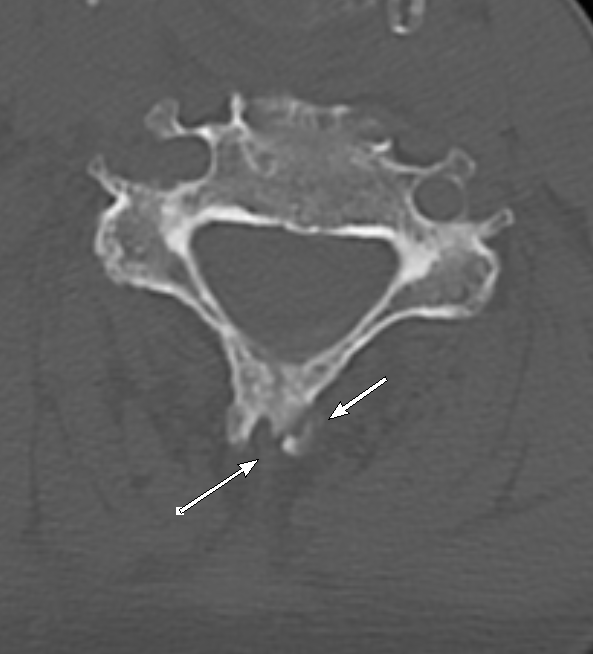

#easytomiss fracture of a bifid spinous process#spine#trauma#radiology#radres This fracture can be overlooked if you are focusing only on sagittal images#EMRad#FOAMrad#FOAMed@NASSspine https://bit.ly/32bT4VX pic.twitter.com/b0g3MRwzhf